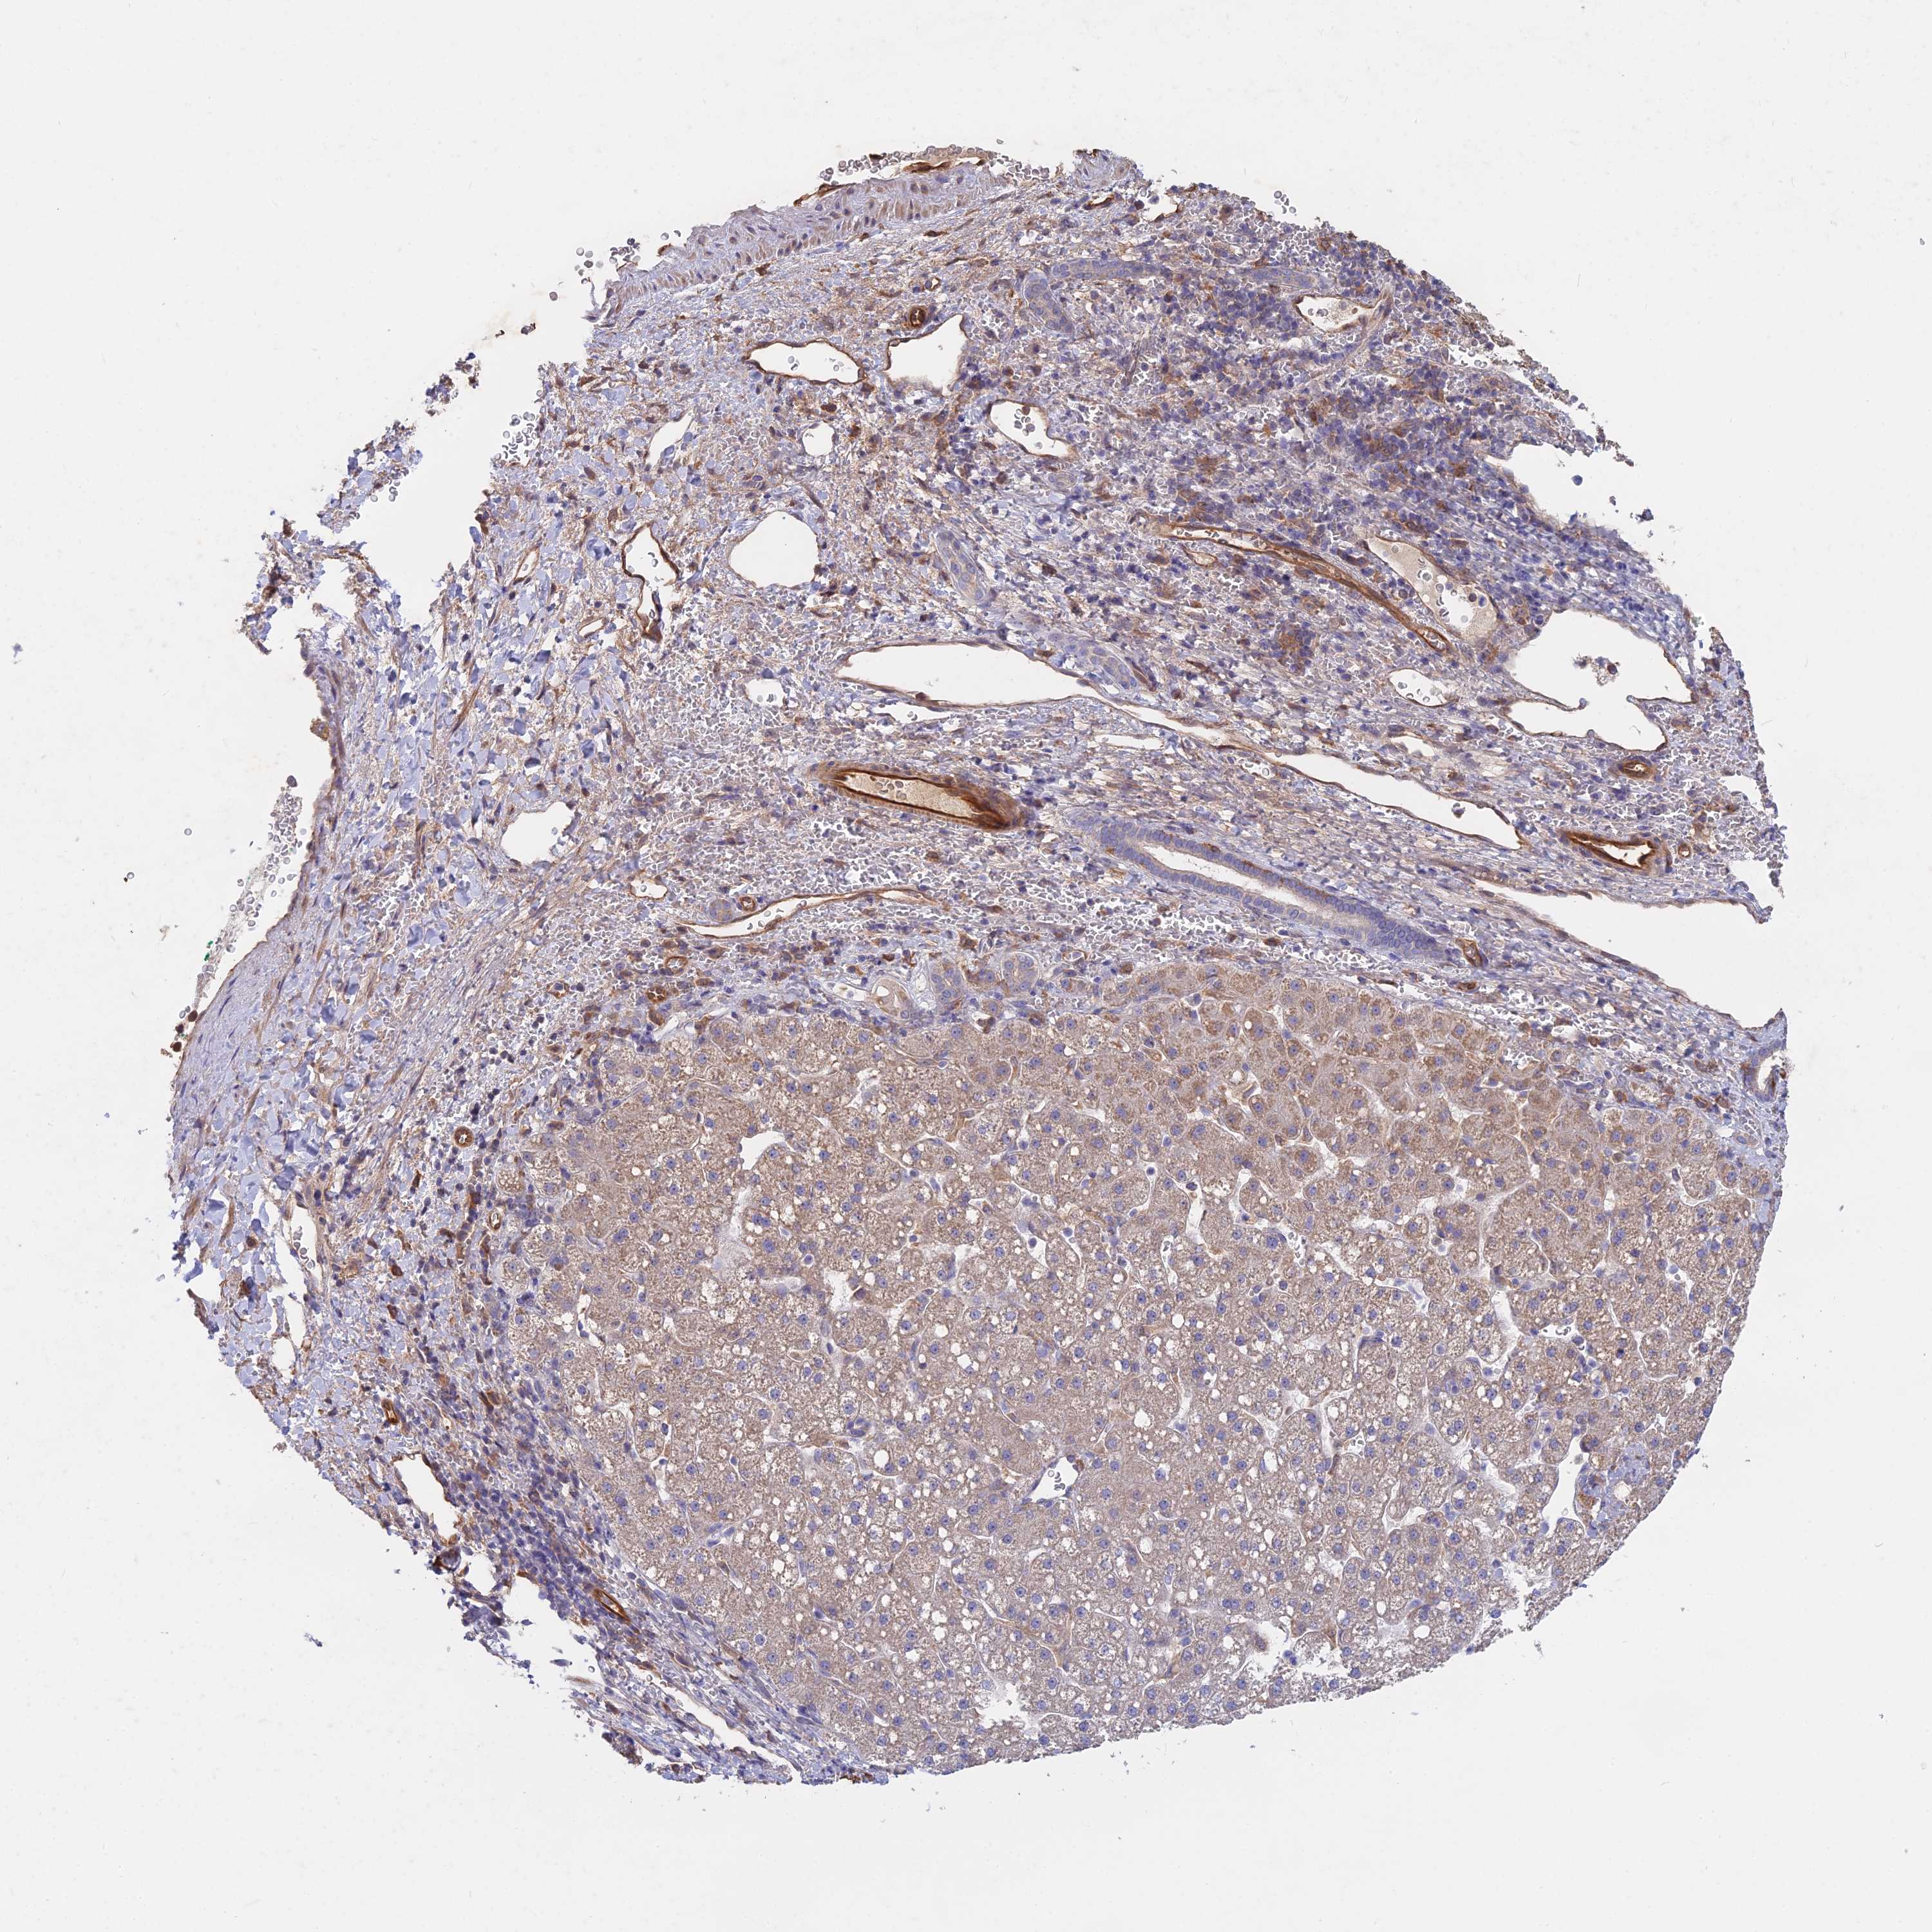

LIVER CANCER - Protein expressioni

A mouse-over function shows sample information and annotation data. Click on an image to view it in a full screen mode. Samples can be filtered based on level of antibody staining by selecting one or several of the following categories: high, medium, low and not detected. The assay and annotation is described here.

Note that samples used for immunohistochemistry by the Human Protein Atlas do not correspond to samples in the TCGA dataset.

Antibody stainingi

Antibody staining in the annotated cell types in the current human tissue is reported as not detected, low, medium, or high, based on conventional immunohistochemistry profiling in selected tissues. This score is based on the combination of the staining intensity and fraction of stained cells.

Each image is clickable and will lead to virtual microscopy that enables deeper exploration of all samples and also displays staining intensity scores, fraction scores and subcellular localization as well as patient and tissue information for each sample.

Antibody HPA042677

Staining

High

Medium

Low

Not detected

Intensity

Strong

Moderate

Weak

Negative

Quantity

>75%

75%-25%

<25%

None

Location

Nuclear

Cytoplasmic/membranous

Cytoplasmic/membranous,nuclear

Cholangiocarcinoma

Carcinoma, Hepatocellular, NOS